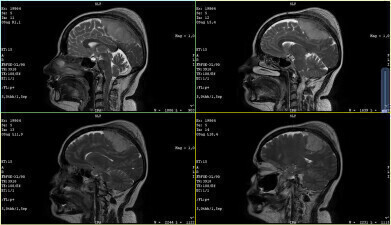

Meningioma of the sagittal sinus. Credit: Wikimedia Commons